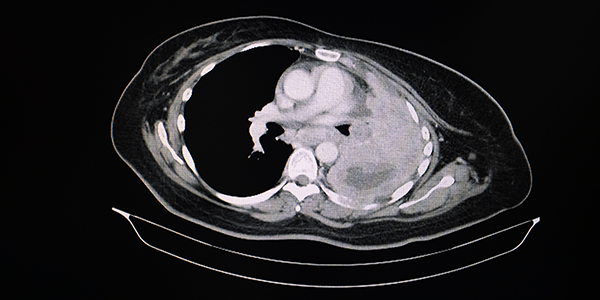

Marklin GF, O'Sullivan C, Dhar R.

Ventilation in the prone position improves oxygenation and results in more lungs being transplanted from organ donors with hypoxemia and atelectasis.

Journal of Heart and Lung Transplantation 2021; 40:120-127. https://doi.org/10.1016/j.healun.2020.11.014.

The value of the prone position as a means of improving oxygenation is now common knowledge following its widespread use during the COVID-19 pandemic. The authors of this paper studied the use of the prone position in consented DBD donors on the PaO2/FiO2 ratio and reduction in atelectasis. Patients in the prone position for 12 hours or longer had significantly more improved PaO2/FiO2 ratio and less atelectasis on CT scan than those left in the supine position. More importantly the utilisation of lungs for transplantation was increased significantly from 24% in the supine group to 45% in the prone group. The study was small (40 patients proned) and difficult to blind, but the results are impressive for a simple, and now well drilled ICU procedure. The impact of this intervention on the family is one issue that needs consideration on a case by case basis.